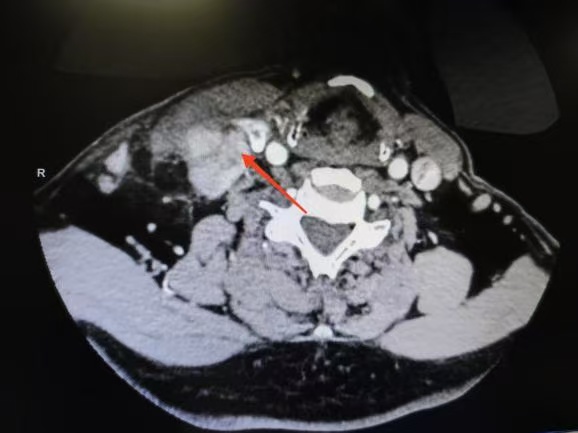

CT箭頭所示:右側(cè)甲狀腺腫瘤

CT箭頭所示:側(cè)頸區(qū)轉(zhuǎn)移淋巴結(jié)